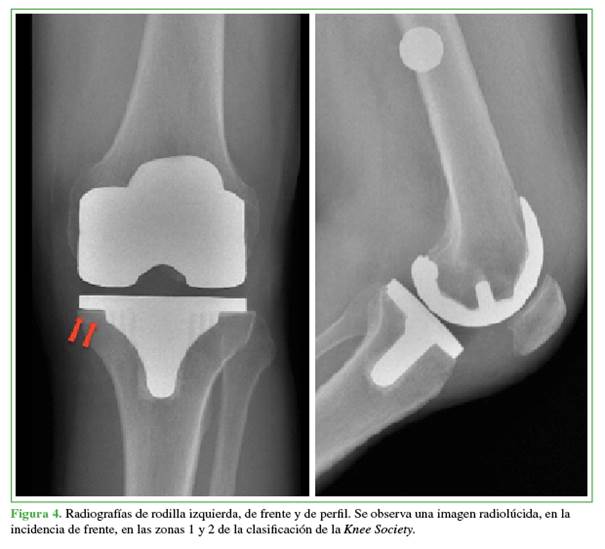

El paciente continuó́ el tratamiento antibió́tico por siete semanas y, a la semana 10, ante la buena evolució́n clínica y el descenso de los parámetros infecciosos, se decidió́ realizar el segundo tiempo de la revisió́n. No se observaron cambios patoló́gicos en el tejido periprotésico, algo que fue confirmado mediante el análisis histopatoló́gico. Se extrajo el espaciador y se implantó́ una pró́tesis de revisió́n cementada con liner constreñido y vástagos (Triathlon®, Stryker, EE.UU.) tanto en el fémur como en la tibia (Figura 7).